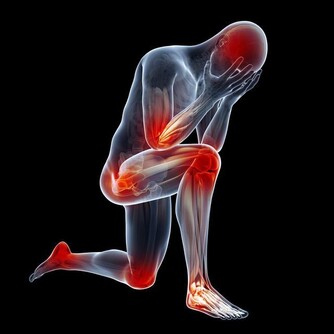

研究證明,中等運動強度的活動者,患腦血管疾病的風險比體力活動不足者明顯減少。科學運動有助於改善腦血管狀況,改變血管彈性,促進全身的血液循環,從而提高大腦血流量。運動方式和運動量可以根據自身條件去選擇,散步、慢跑、游泳、騎自行車、打太極拳等,都是較好的有氧運動。運動時不用太劇烈,每天堅持1次,每次半小時左右,運動量以心跳增加10次左右為宜,長期堅持能幫助延緩腦血管的衰老。